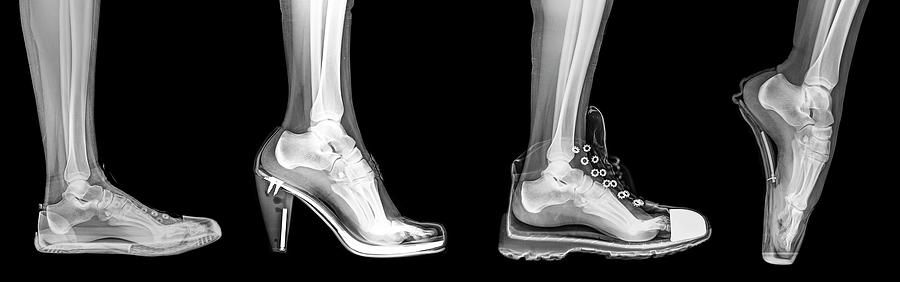

How your feet look when you wearing high heels!

The higher the heel, the pressure gets shifted forward, and the more weight. Your knees and hips then have to push forward and your back has to hyperextend backward to counterbalance. This can translate to the leg, hip, and back pain. It misaligns the whole skeletal system and that's in a nutshell w

It misaligns the whole skeletal system and that's in a nutshell why it's really bad for you.

The higher the heel, the pressure gets shifted forward, and the more weight. Your knees and hips then have to push forward and your back has to hyperextend backward to counterbalance. This can translate to the leg, hip, and back pain. It misaligns the whole skeletal system and that's in a nutshell why it's really bad for you.